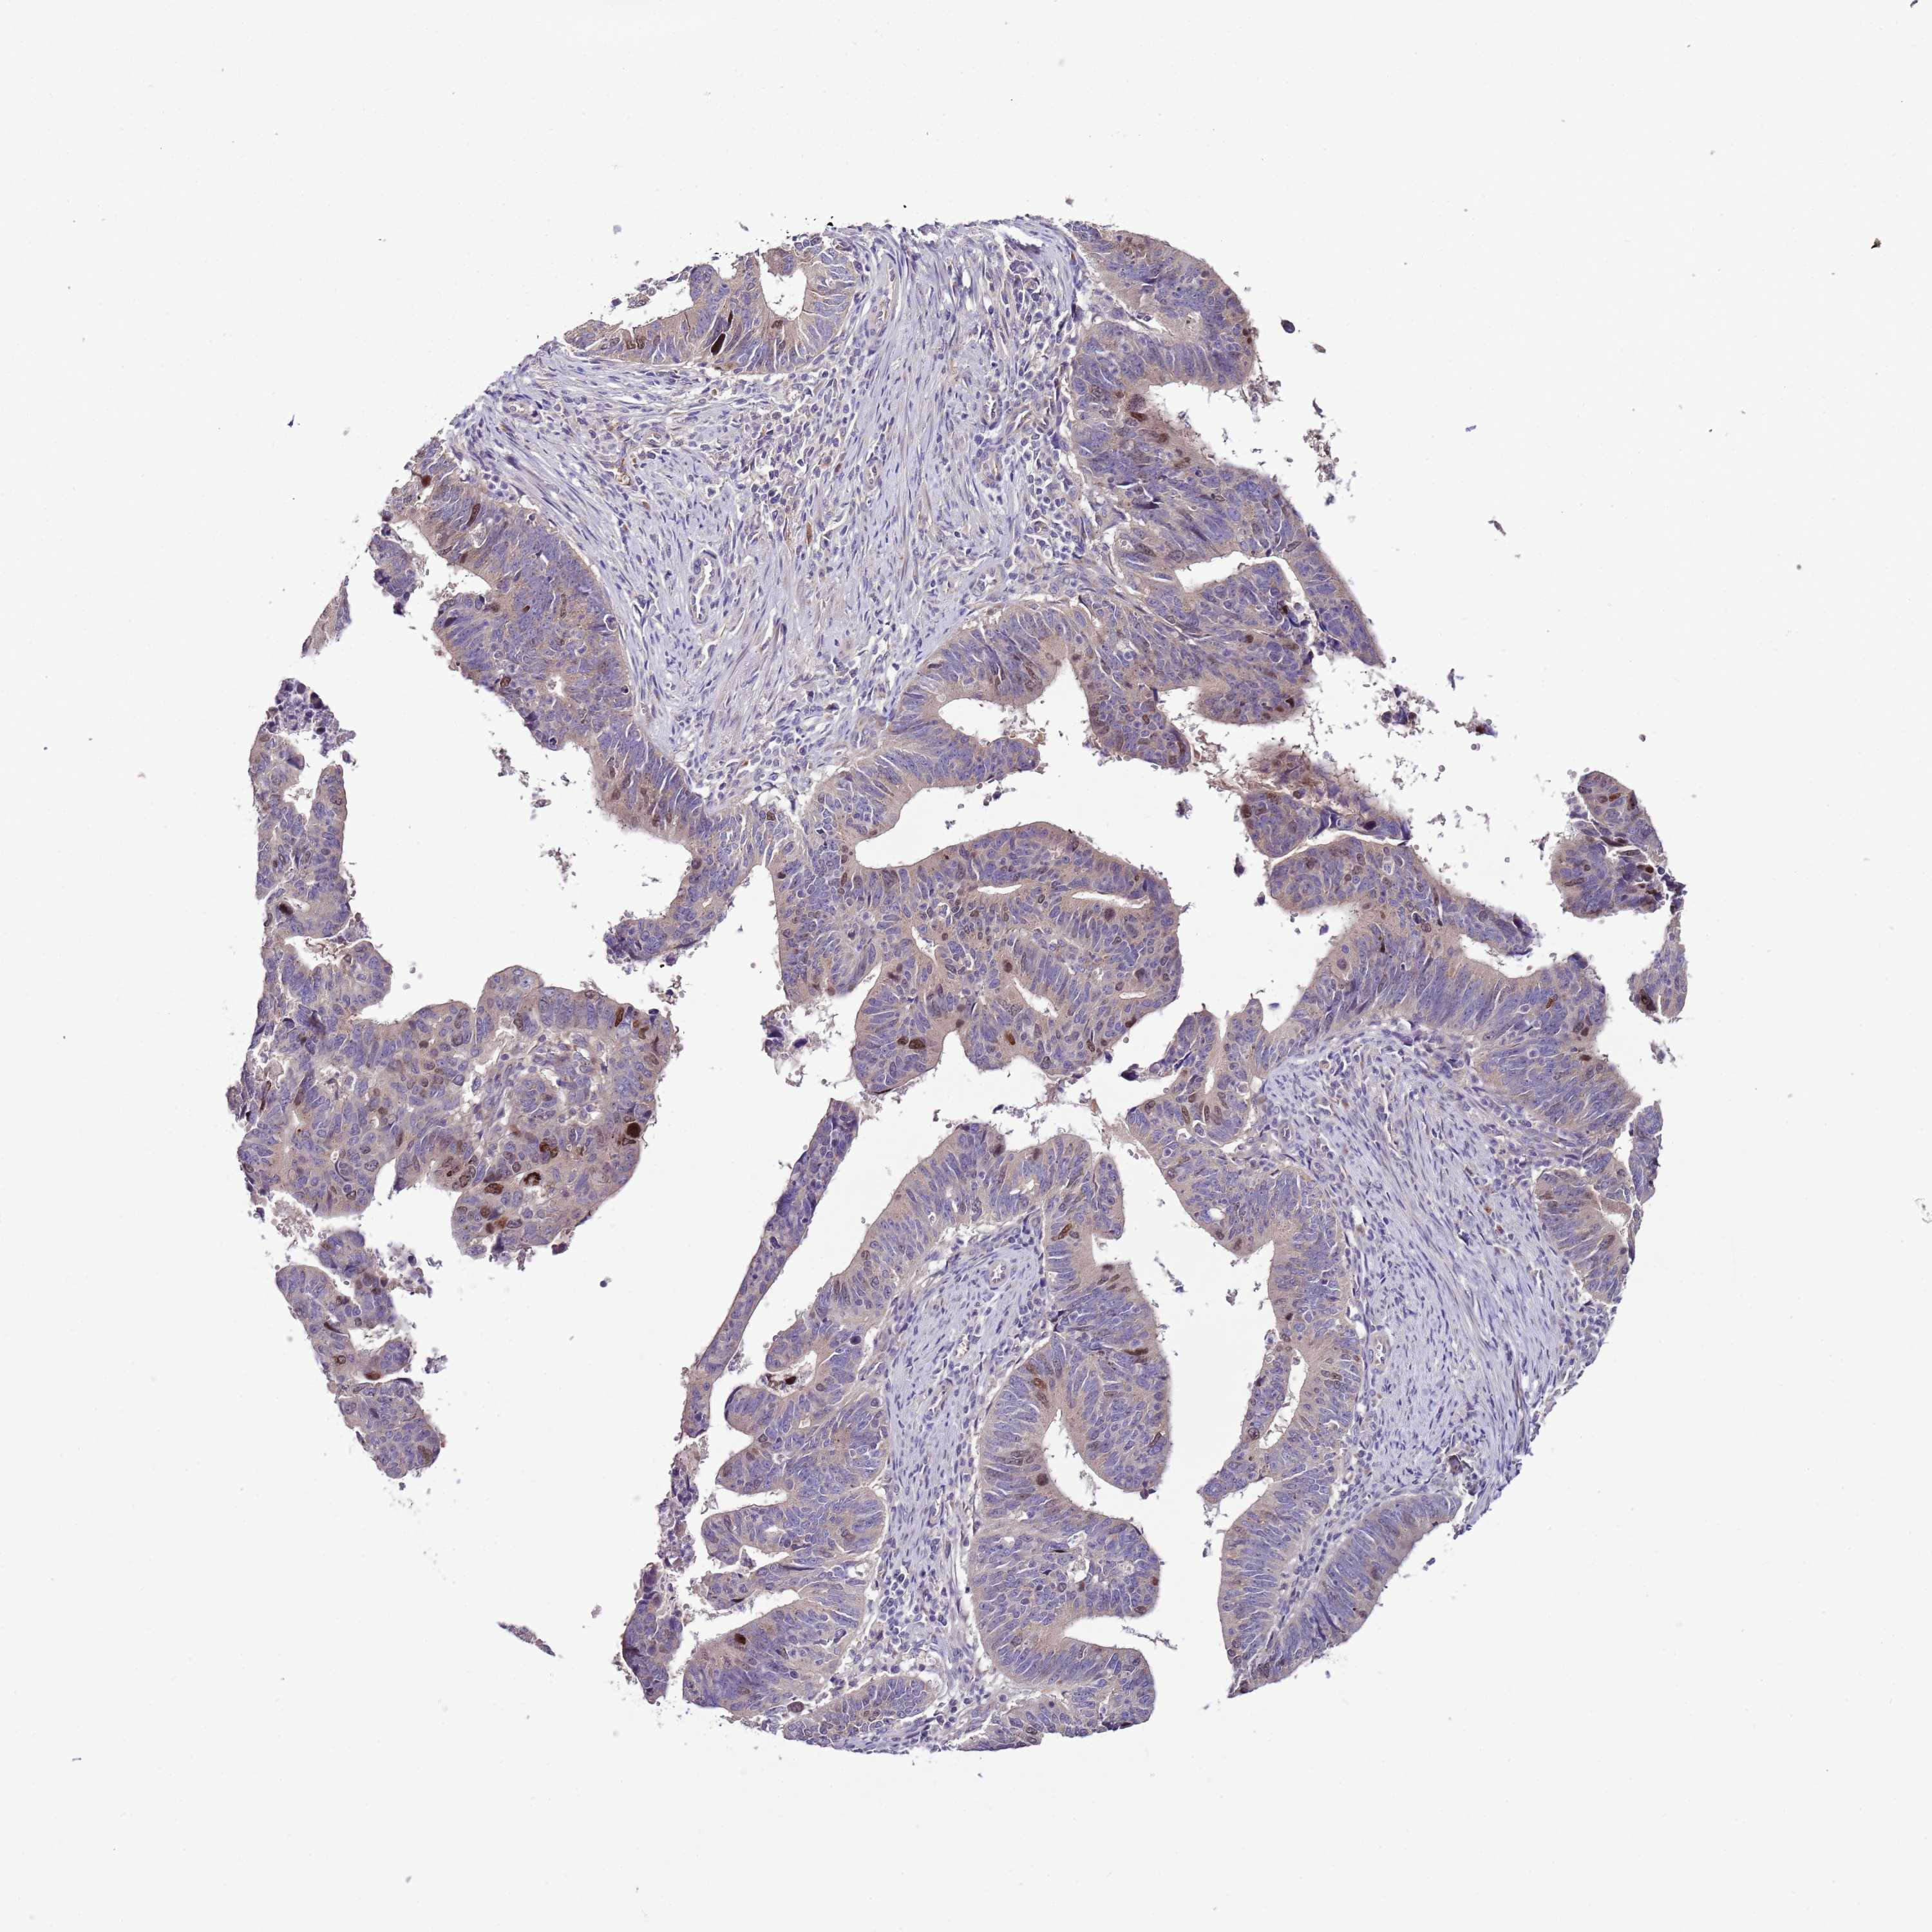

STOMACH CANCER - Protein expressioni

A mouse-over function shows sample information and annotation data. Click on an image to view it in a full screen mode. Samples can be filtered based on level of antibody staining by selecting one or several of the following categories: high, medium, low and not detected. The assay and annotation is described here.

Note that samples used for immunohistochemistry by the Human Protein Atlas do not correspond to samples in the TCGA dataset.

Antibody stainingi

Antibody staining in the annotated cell types in the current human tissue is reported as not detected, low, medium, or high, based on conventional immunohistochemistry profiling in selected tissues. This score is based on the combination of the staining intensity and fraction of stained cells.

Each image is clickable and will lead to virtual microscopy that enables deeper exploration of all samples and also displays staining intensity scores, fraction scores and subcellular localization as well as patient and tissue information for each sample.

Antibody HPA048964

Staining

High

Medium

Low

Not detected

Intensity

Strong

Moderate

Weak

Negative

Quantity

>75%

75%-25%

<25%

None

Location

Nuclear

Cytoplasmic/membranous

Cytoplasmic/membranous,nuclear

Adenocarcinoma, NOS